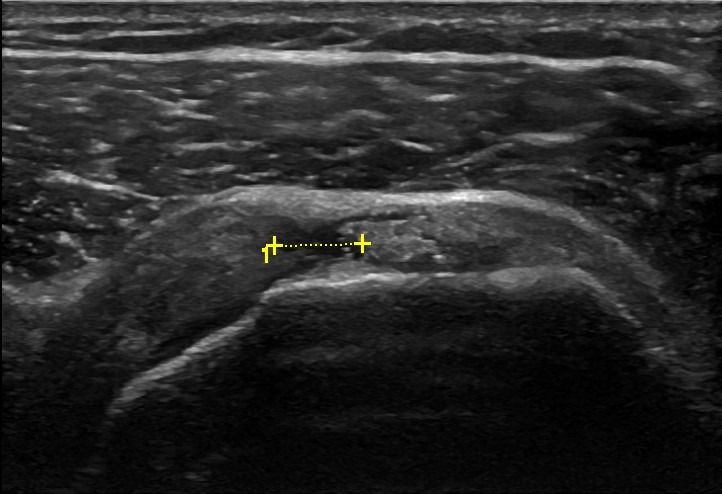

Το Υπερηχογράφημα Ώμου επιτρέπει τον εντοπισμό παθήσεων στους τένοντες του στροφικού πετάλου, όπως:

- Ασβεστοποιός Τενοντίτιδα

- Ρήξη των τενόντων (υποπλάτιος, υπερακάνθιος, υπακάνθιος και ελάσσων στρόγγυλος τένοντας)

Επιπλέον, το Υπερηχογράφημα Ώμου μπορεί να διαγνώσει τενοντοπάθεια, τενοντοελυτρίτιδα ή ρήξη στον τένοντα της μακράς κεφαλής δικέφαλου βραχιονίου.